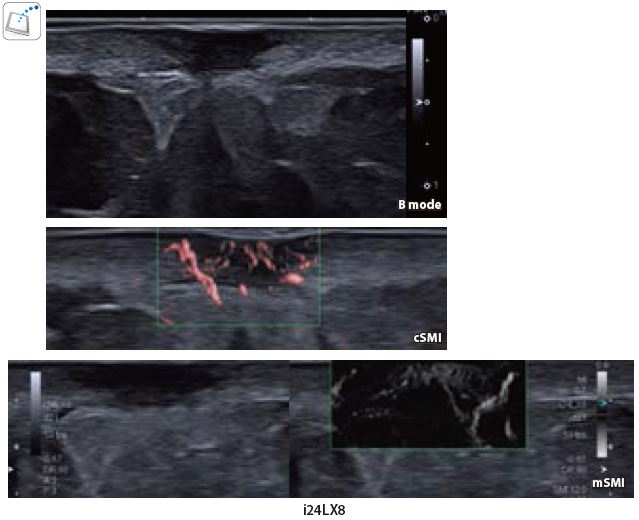

Випадок 2: Інфікована злоякісна виразка шкіри

Безпрецедентна якість доплерівського зображення на i24LX8 в ближньому поліпродемонстрована на цій інфікованій злоякісній виразці шкіри. cSMI і mSMI відображає розгалужену багату гіперваскулярну мережу капілярів з високою роздільною здатністю, яка не може бути виявлена при більш низькій частоті.

Мал. 11.